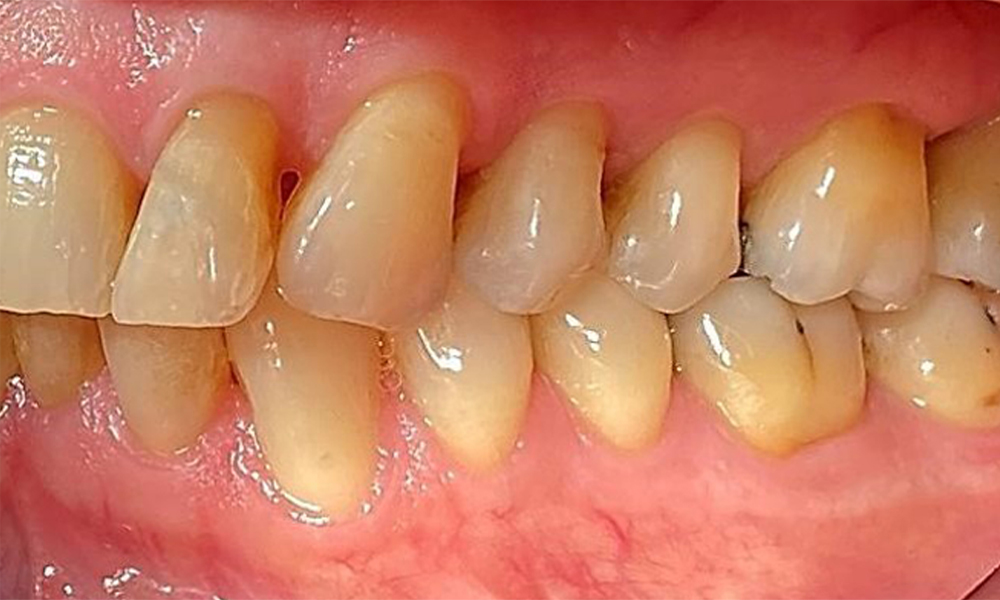

Right lateral view. Loss of the interdental papillae.

Fig. 3 Right lateral view. Loss of the interdental papillae. © Dr R. Krapf

The patient has a full dentition with 28 teeth, which includes amalgam and composite fillings in the molar and premolar regions. There is a visible clinical marginal gap present on tooth 14. Tooth 27 has an adequate gold inlay. There are also generalized attritions and abrasions. (Fig. 2, Fig. 3, Fig. 4, Fig. 5, Fig. 6)

Periodontal findings

The patient has stage II, grade B periodontitis (5). At 1 to 3 mm, the clinical probing depths were within the physiological range. Localized probing depths of 5 mm were observed on the mesiopalatal aspects on both 17 and 27. There are generalized recessions of 1–3 mm with partial loss of the interdental papillae (Fig. 2, Fig. 3, Fig. 4)